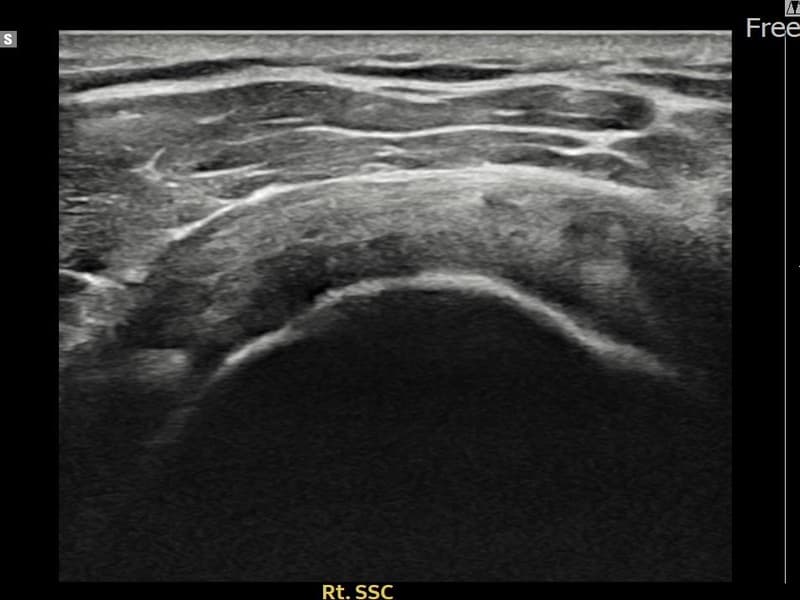

超音波検査にて右 견갑하근건 関節面側部分断裂(7mm × 3mm (腱厚の約28%欠損))を確認。縫縮術施行後、腱の連続性が回復し、日常生活に復帰されました。

施術前

術前超音波にて右 견갑하근건 関節面側部分断裂・右肩棘上筋腱のエコー不連続と腱欠損(7mm × 3mm (腱厚の約28%欠損))を確認。術後超音波では断裂部位が再生組織で充填され、腱の連続性回復とエコーパターンの正常化が確認されました。

持続する右肩痛で来院された患者様です。超音波検査にて右 견갑하근건 関節面側部分断裂(欠損:7mm × 3mm (腱厚の約28%欠損))を確認し、超音波ガイド下で非手術的縫縮術を施行しました。術後は約4〜6週間のブレース装着の後、段階的なリハビリプログラムを実施。経過超音波で腱の連続性回復を確認し、患者様は無事に日常生活へ復帰されました。